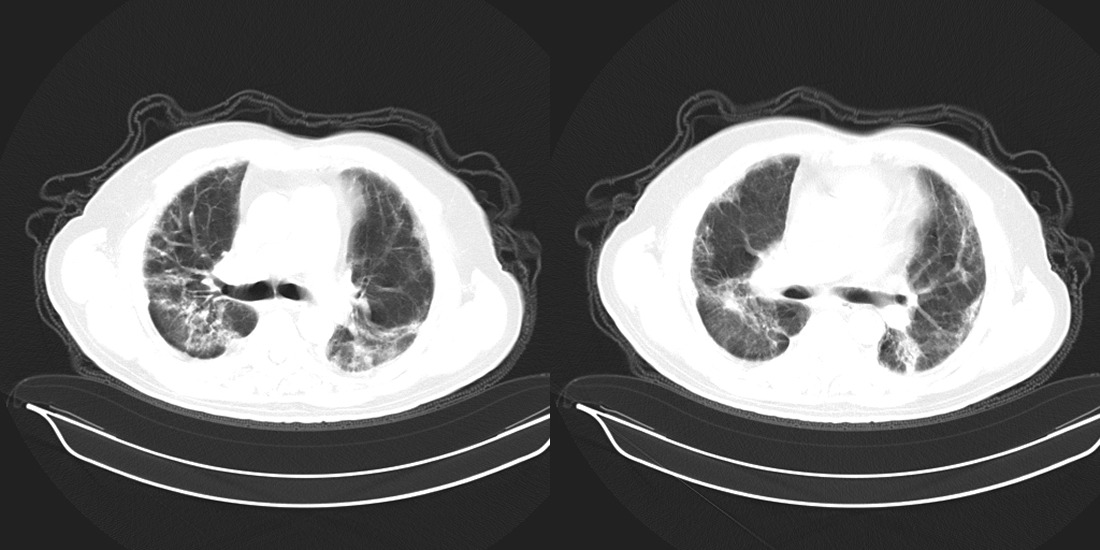

以下是引用zsl6918在2008-2-14 12:15:00的发言:[br]慢支并感染,肺气肿,肺间质纤维化,肺动脉高压。

以下是引用liuyue在2008-2-14 17:25:00的发言:[br]慢支并感染,肺气肿,肺间质纤维化,肺动脉高压 .肺大泡.[br]

以下是引用随光逐影在2008-2-15 11:10:00的发言:[br]1)慢性支气管炎并肺部感染。2)肺间质纤维化。3)肺气肿(多发性肺大泡形成)。4)肺动脉高压。